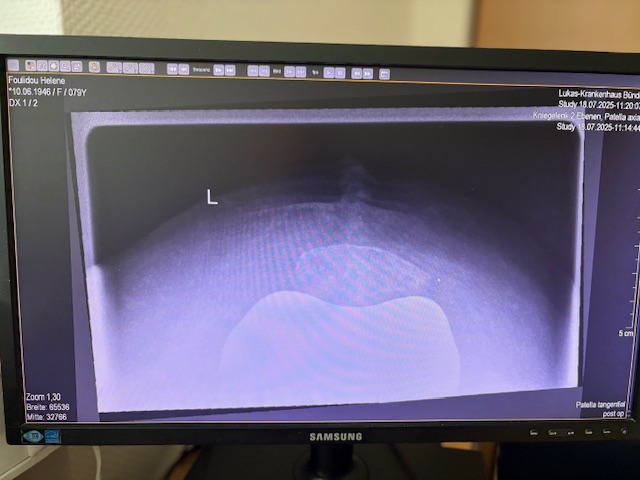

Η 80χρονη ασθενής παρουσίαζε έντονο πόνο και δυσκαμψία στο αριστερό γόνατο τα τελευταία χρόνια. Ο πόνος είχε επιδεινωθεί, επηρεάζοντας τη βάδιση και τη συνολική κινητικότητα, ενώ δυσκολευόταν ακόμα και σε απλές δραστηριότητες όπως το ανέβασμα σκαλοπατιών ή το περπάτημα σε μικρές αποστάσεις. Με την υπάρχουσα πρόθεση ισχίου στην αριστερή πλευρά η ασθενής ήταν αρκετά ευχαριστημένη. Ο ακτινολογικός και κλινικός έλεγχος ανέδειξε προχωρημένη οστεοαρθρίτιδα του αριστερού γόνατος, με πλήρη απώλεια του αρθρικού χόνδρου και παραμόρφωση του μηροκνημιαίου άξονα. Μετά από ανάλυση όλων των επιλογών, αποφασίστηκε η Ολική Αρθροπλαστική Γόνατος με Ρομποτική Υποβοήθηση, με στόχο την απόλυτη ακρίβεια στην τοποθέτηση των εμφυτευμάτων και την αποκατάσταση της φυσιολογικής μηχανικής του γόνατος.

Ο προεγχειρητικός ψηφιακός σχεδιασμός

Πραγματοποιήθηκε σε ειδική ακτινογραφία ολόκληρων των δύο κάτω άκρων. Σε αυτό το ψηφιακό μοντέλο σχεδιάστηκε με ακρίβεια το είδος, το μέγεθος και η ακριβής θέση των προθέσεων, με βάση τα ανατομικά χαρακτηριστικά της ασθενούς.